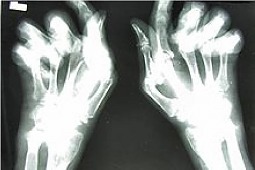

Reumatoidalne zapalenie stawów